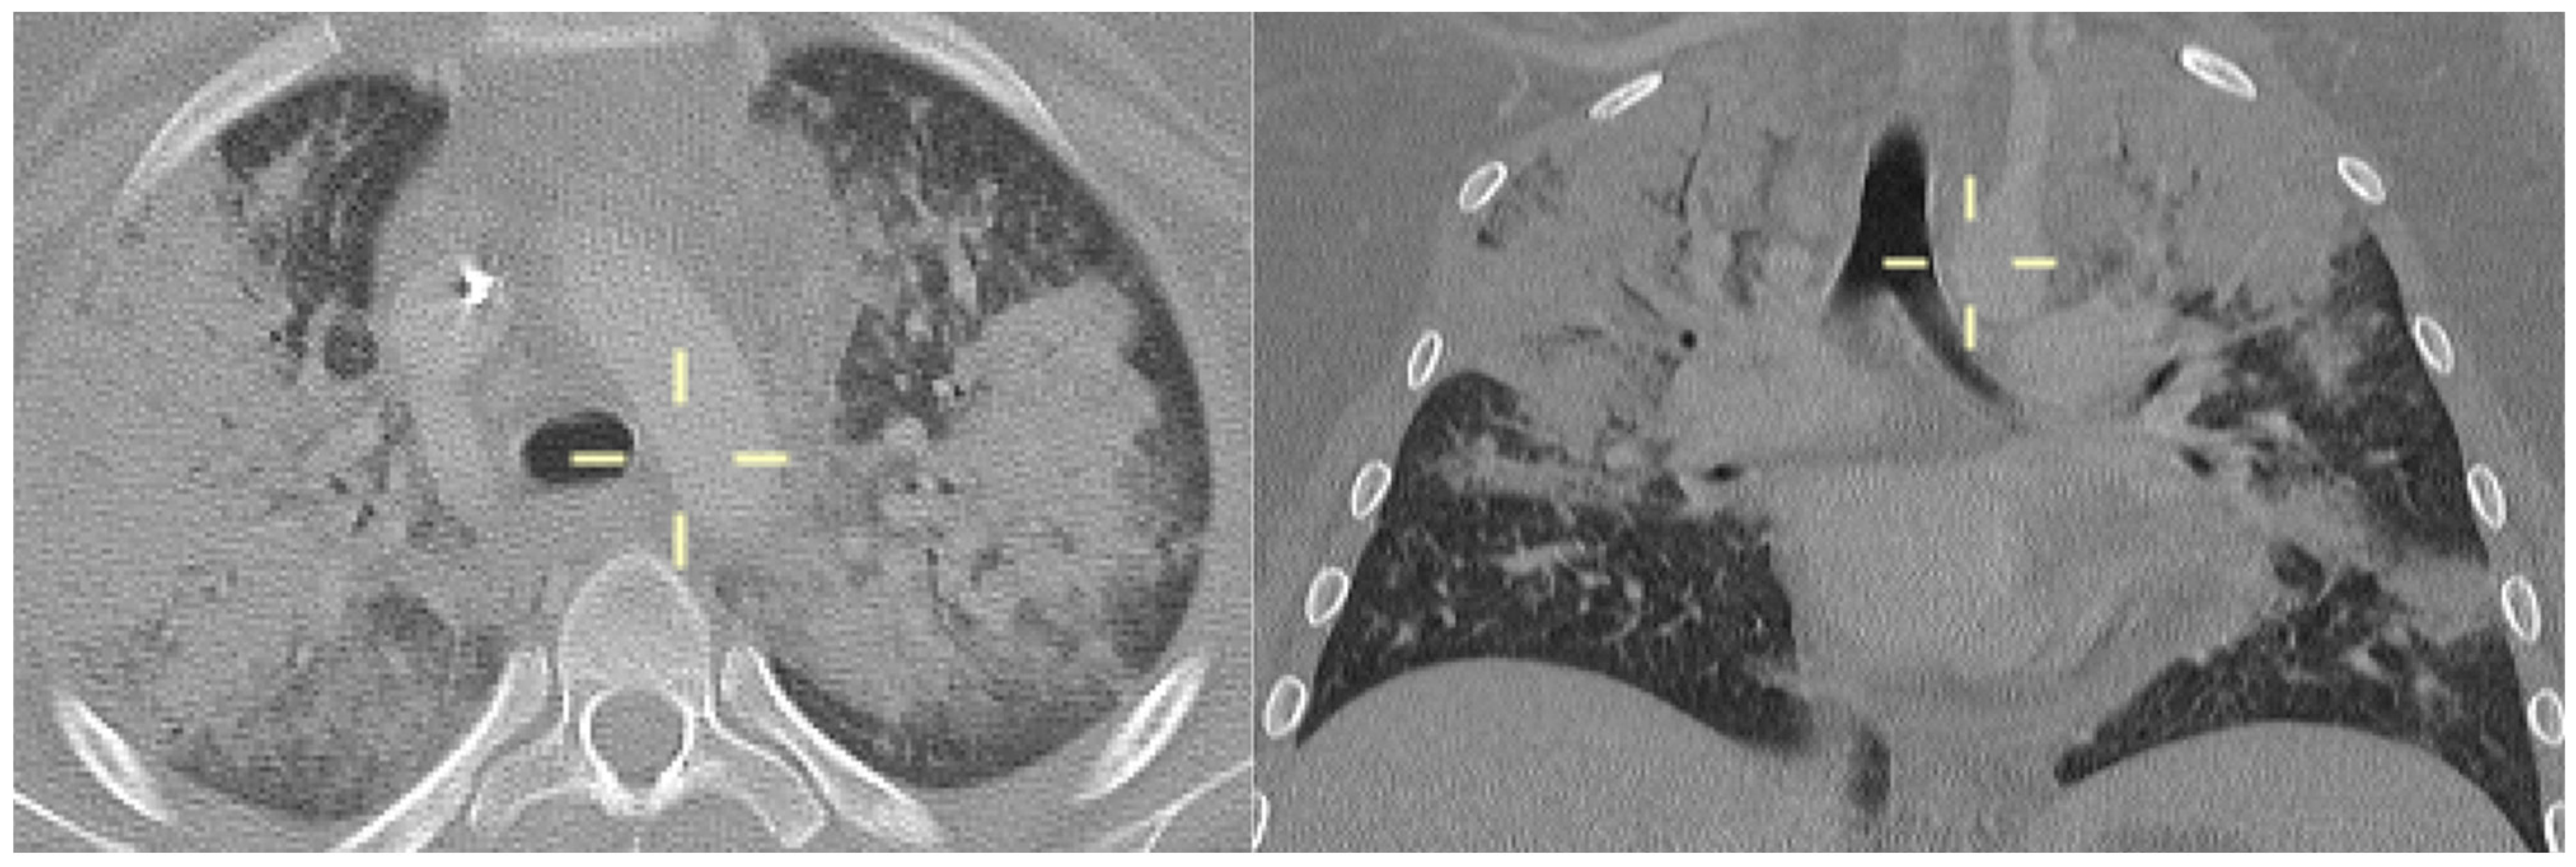

3.5. Radiological Features of PJP in the Study Population